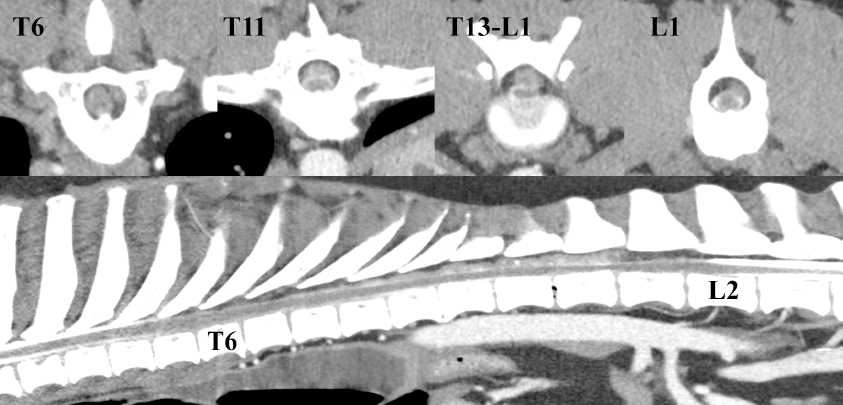

Axial computed tomography (CT) with lumbar myelography (Phillips Brilliance TM CT 16, Phillips GmbH Market DACH Healthcare, Hamburg, Germany) under general anesthesia revealed dorsal to dorsolateral, mostly left-sided extradural spinal cord compression, extending from Th6 to L1 (Fig. 1). The degree of extradural spinal cord compression varied between 20% and 50% of the cross area of the spinal canal, being most pronounced at Th13-L1. The extradural compressive mass was mostly homogenous in appearance with a mean Hounsfield Unit (HU) of 54, slightly higher than the spinal cord (42 HU). At some locations, small hyperdense bodies within the mass were also visible. At the intervertebral space Th13-L1, a vacuum phenomenon was also noted. No further abnormalities were detected. Based on CT-myelography and the results of clinical history and physical examination, DEEH was suspected, but the most likely differential diagnosis at this point included, among others, malignancy and coagulopathy. Because mucosal bleeding time, as well as full coagulation profile, revealed no abnormalities, coagulopathy was excluded from the list of differential diagnoses.

Fig. 1. Preoperative CT myelographic images. Note the extent of dorsal to dorsolateral left-sided extradural compression, starting at Th6 and reaching until L1. Spinal compression was most severe at the Th13-L1 level, reaching about 50%.